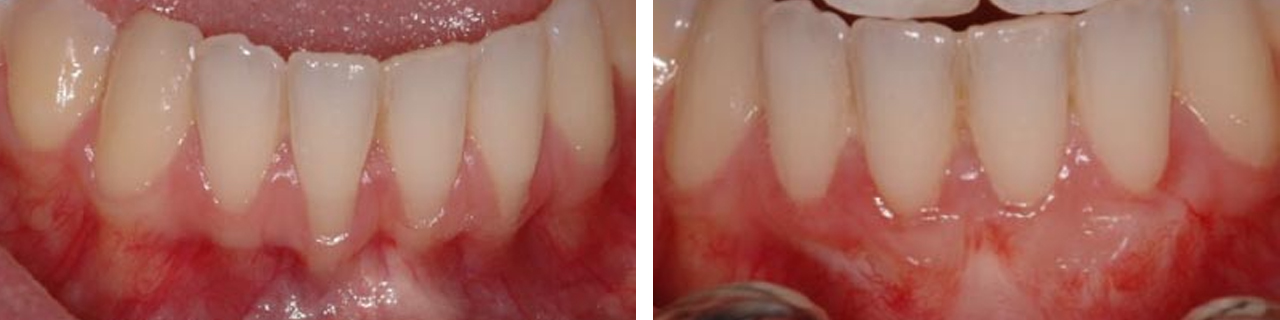

Cubrimiento de raíces expuestas.

Cubrimiento de raíces expuestas y aumento del grosor de la encía.